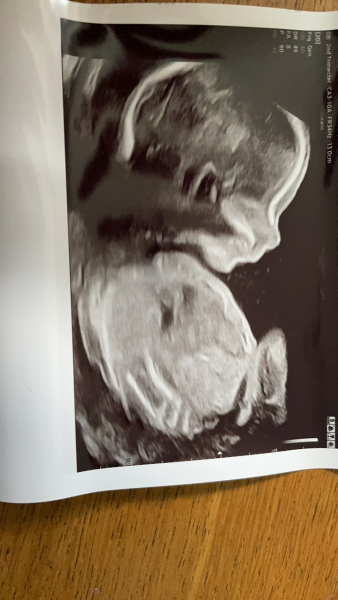

Had scan yesterday though and all is well! We’re team 🟡 but been trying to still guess all day

Amy1303 · 11/11/2022 14:31

Hope everyone's 20 week scans went well. I'm due 27th of March and we are keeping gender a surprise but any guesses welcome 🙈 xx

Due March 2023 - thread 4